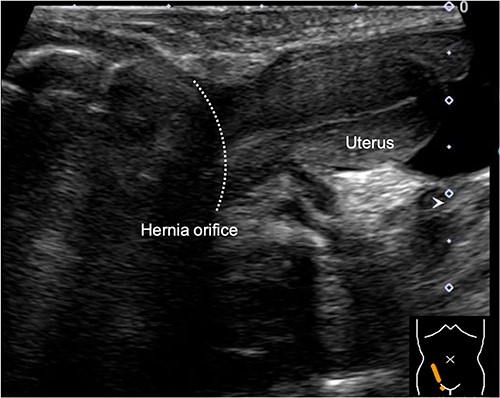

During the newborn’s stay in the NICU, both inguinal regions showed swelling. An ultrasound examination conducted when the infant was 3 months old revealed bilateral inguinal hernias, with the uterus herniating on the right side (Fig. 1). There were no signs of incarcerated hernia, and the urgency of the situation was considered low. As a result, the patient was discharged from the NICU and received outpatient care. At 11 months of age, ultrasound examination was performed, which revealed the presence of omental herniation but no evidence of uterine prolapse (Fig. 2).

Sagittal view of the inguinal ultrasound at 3 months of age, revealing the presence of uterus protruding into the hernial sac.